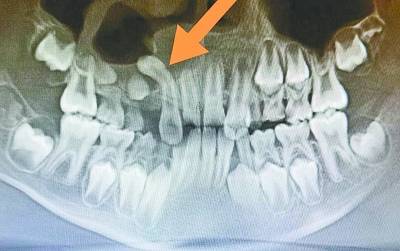

“翻跟头”的多生牙 。

经多方打听 , 洋洋的妈妈李女士找到了省妇幼保健院口腔科副主任医师吴茜主任求诊 。 8月21日 , 吴茜面诊之后 , 先让洋洋拍了一个口腔CT定位多生牙 , 发现腭侧多生牙位于上颌窦底 , 与上颌窦穿通 , 并呈180度倒置反转 。 而且 , 这颗多生牙还“鸠占鹊巢” , 挤占了右上尖牙的位置 , 导致右上尖牙牙胚高位阻生 。